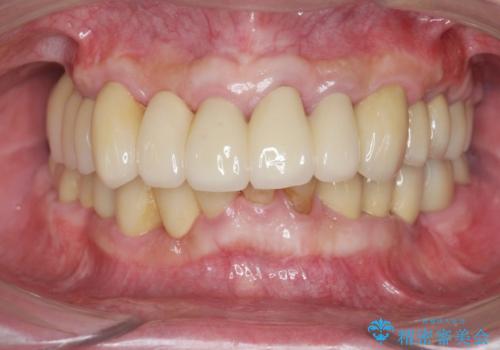

歯周外科を行ったことで非常に安定した歯周環境となり、引き締まった歯ぐきとなりました。

歯周病治療を伴う前歯審美セラミック治療

セラミック治療を行う前に歯周病の問題を解決すべく歯周外科を行い歯周ポケットを除去し整備したのちセラミックブリッジ・クラウンの製作を行います。